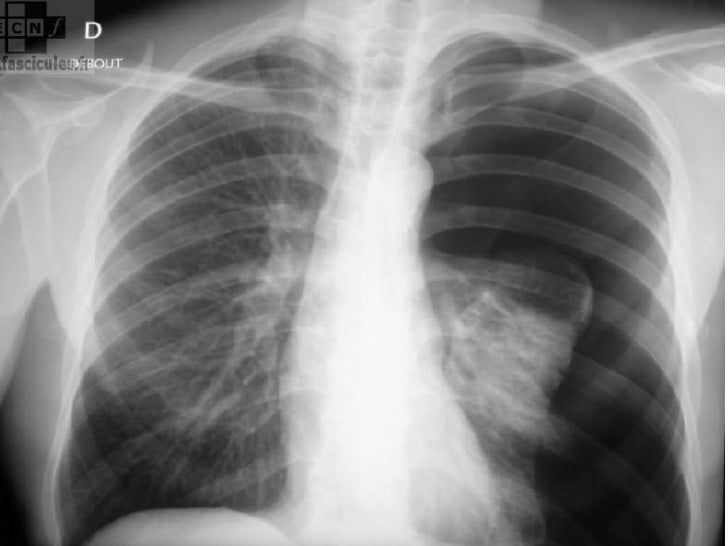

Par ailleurs, le poumon associé à un emphysème s’infecte plus facilement Différents examens permettent d’évaluer l’importance de l’emphysème et son impact scanner, fonctions pulmonaires, analyses de laboratoires, épreuves fonctionnelles Le traitement de base de l’emphysème dépend avant tout de sa cause. L’apparition d’emphysème et de grosses bulles (diamètres compris entre 0,3 cm et 12 cm) est probante chez les premiers et quasi absente chez les seconds (présence de bulles inférieures à 1cm de diamètre sans emphysème significatif) Il est tentant de conclure à la responsabilité du cannabis dans l’apparition de ces pathologies. La bulle d’emphysème était à droite dans 5 cas et à gauche dans 2 cas La symptomatologie principale était une douleur thoracique avec dyspnée Tous les patients ont eu un scanner thoracique objectivant une bulle d’emphysème qui est le siège d’un niveau hydroaérique Cinq patients ont eu une bullectomie avec avivement pleural.

Le cancer sur bulle d’emphysème est décrit comme rare dans la littérature, mais sa fréquence est possiblement sousestimée Il s’agit d’un adénocarcinome dans 85 % des cas Cette entité ne doit pas être méconnue et une TEPFDG est indiquée dans le bilan initial d’une bulle d’emphysème à paroi épaissie. Many translated example sentences containing "bulle d'emphysème" – EnglishFrench dictionary and search engine for English translations. Figure 2 bulle d’emphysème de l’apex pulmonaire I3 PNO traumatique Consécutif à une effraction de la plèvre viscérale par traumatisme direct ou indirect iatrogène (ponction transthoracique, ponction pleurale, voie veineuse centrale, etc ) Traumatismes fermés du thorax.